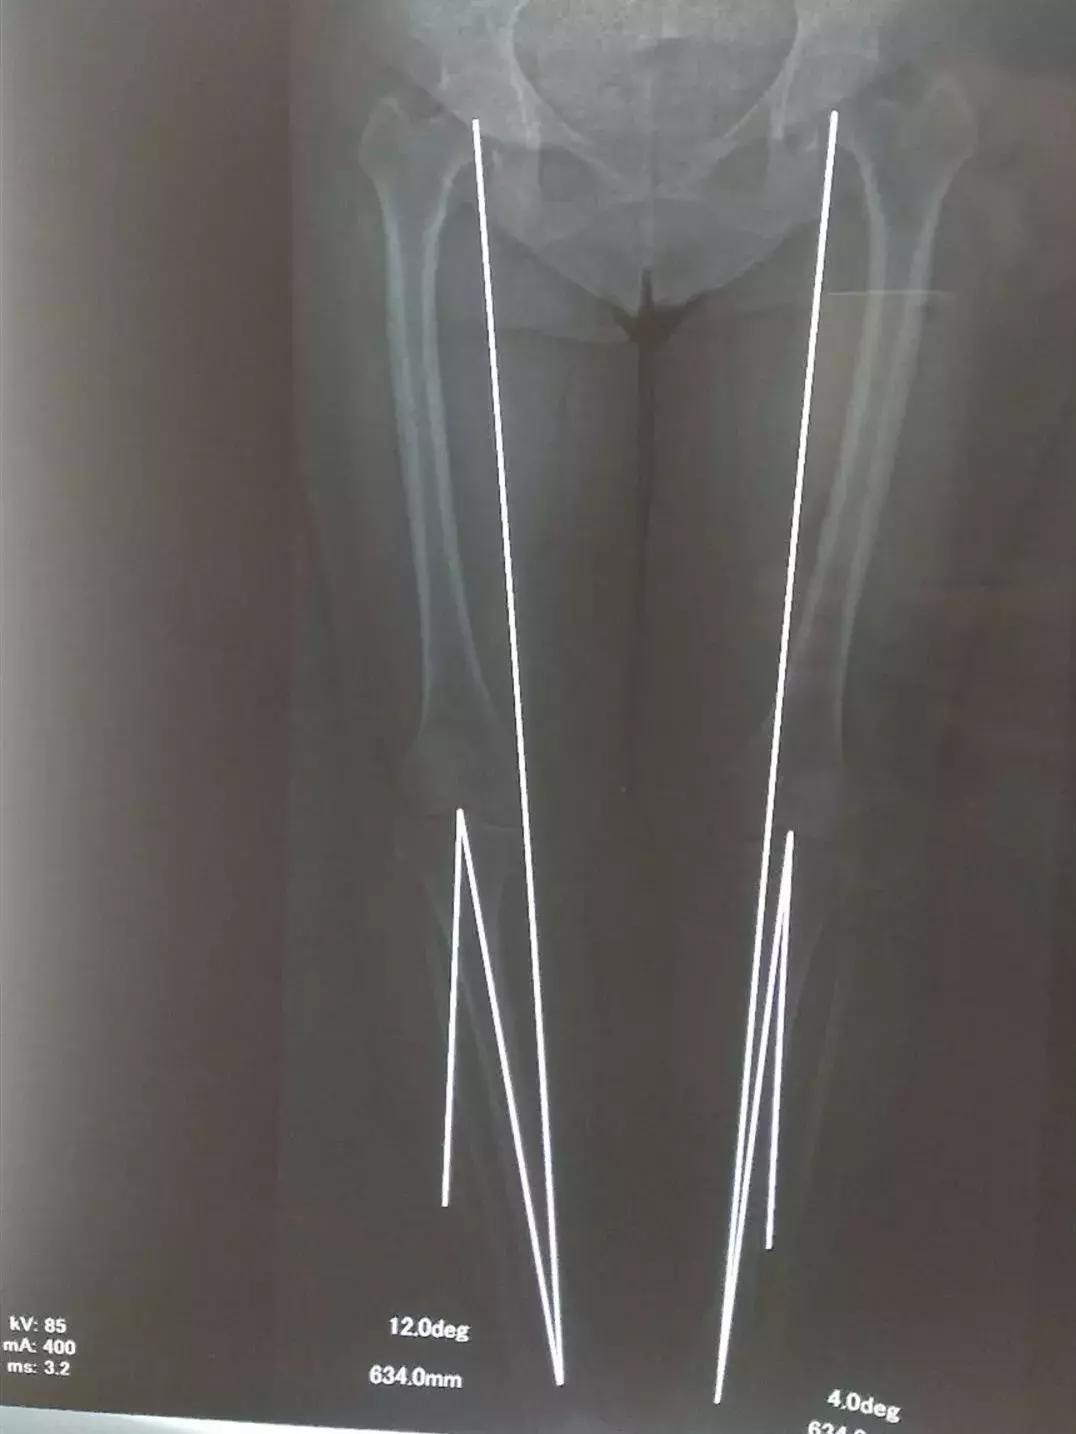

患者是一名中老年女性,患有严重的膝关节退变性骨关节炎,右膝关节明显内翻畸形,膝关节内侧疼痛伴明显活动受限,影响日常生活,曾就诊于省内多家医院,中药西药吃了一大堆,关节内还注射了润滑剂,采取保守治疗效果不佳,很多医院都建议进行关节置换。在得知张云海博士坐诊的消息后,患者抱着很大的希望前来就诊,经过查看病历、X线片、CT片,为改善患者症状,提高患者生活质量,并考虑到患者有强烈的保膝意愿,张云海博士建议患者进行HTO手术治疗。

患者入院后,骨科医护人员根据患者身体症状,完善相关检查,在张云海博士的指导下,邱生海主任及闫煜军主管医师制定了精确而详细的手术方案及术后康复方案。25日,张云海博士为患者实施了HTO手术,骨科医护人员全程配合,手术用时2小时50分,进行顺利。矫正了患者膝关节内翻畸形,恢复了关节的正常力线及功能,缓解了疼痛症状。

HTO手术即胫骨高位截骨术(High Tibial Osteotomy),通过胫骨高位截骨矫形,矫正不良的下肢力线,在骨关节炎没有发展到外侧之前,HTO通过纠正胫骨内翻畸形,把下肢力线适当转移到外侧间室,从而恢复到正常范围,可以有效地阻止软骨的磨损,最终使膝关节疼痛症状明显缓解甚至完全消失,保留了膝关节正常功能,称之为“保膝治疗”。近年来,医疗技术水平的不断提高,HTO手术越来越受骨科医师及患者的青睐。